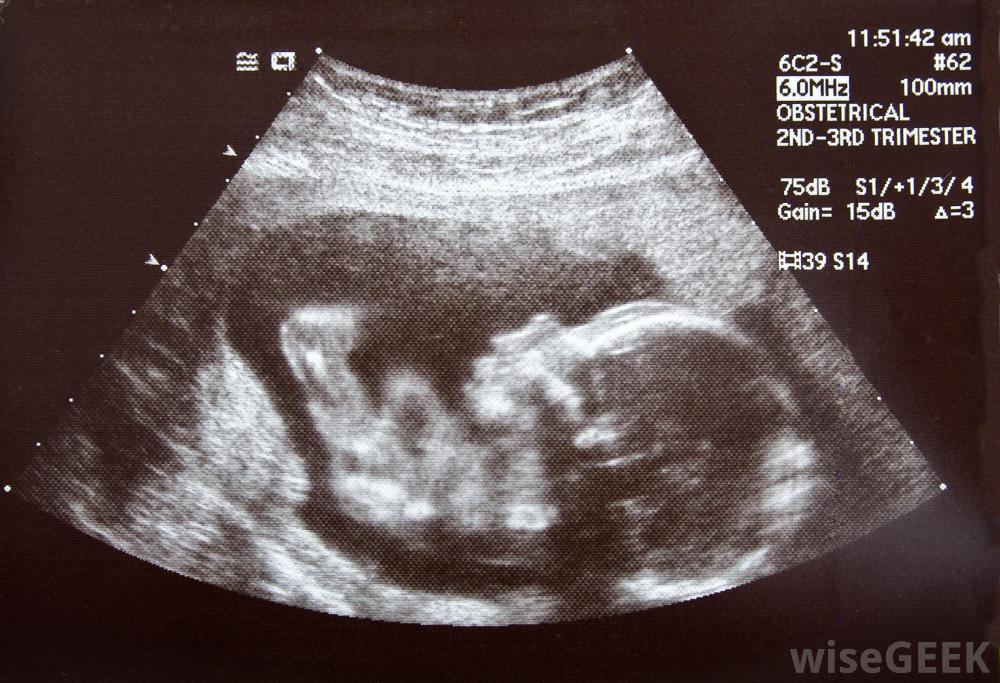

双核畸形是一种罕见的先天性疾病当这种情况在产前超声检查中被发现时,通常建议堕胎。这些胎儿除了颅面重复外,还经常遭受严重的畸形。双极畸形胎儿的脊柱和大脑也有异常。这些婴儿通常两个大脑和两张脸,但这些大脑通常形状不正常。一些双核畸形胎儿的大脑发育不正常,并且患有脑积水。这些婴儿通常在子宫内存活到出生的几率很低,而那些能够存活的婴儿通常在出生后不久存活下来,如果只有一个大脑存在,这些胎儿通常会发育出异常大的头部,这会使自然阴道分娩对母亲造成危险。